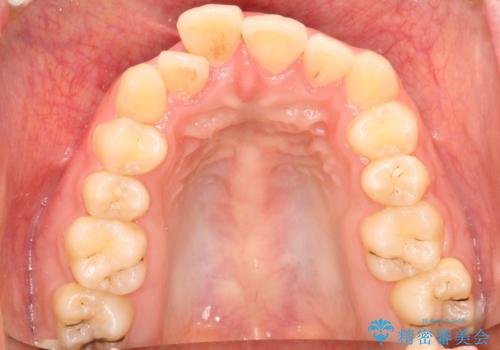

全体的ながたつき ワイヤーによる抜歯矯正で整った歯並びへ

- 上下の全体的ながたつきが気になるとのことで来院されました。

上下左右の前から4番目の歯を抜歯をして、ワイヤー矯正にて並べる計画としました。

患者様が装置を早期に除去したいという希望もあり、少々下の前歯のがたつきが残った状態で矯正を終了しました。

全体的ながたつきがなくなり、見た目の印象がよくなりました。